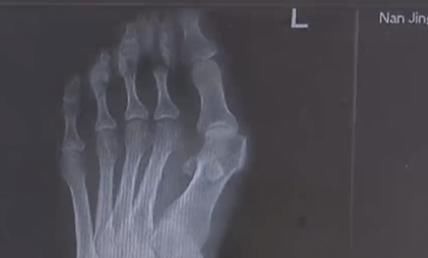

穿高跟鞋是不少女生出门前的必备,今年32岁的王女士十几年前就有了穿高跟鞋的习惯。然而就在最近,自己的脚趾出现了惊人的变化,两边的大脚趾一侧渐渐突起了一个硬疙瘩,走路一久就疼痛不已。

由于高跟鞋的挤压,王女士的左脚大脚趾变成了两个脚趾,随着时间的推移,大脚趾一侧又多了一个 \\\\'\\\\'拐\\\\'\\\\',现在只能通过手术来缓解症状。除了鞋子不当,遗传和疾病因素也是造成拇指外翻的原因,70 岁的高女士患风湿病,脚也发生了接近 60 度的严重变形。